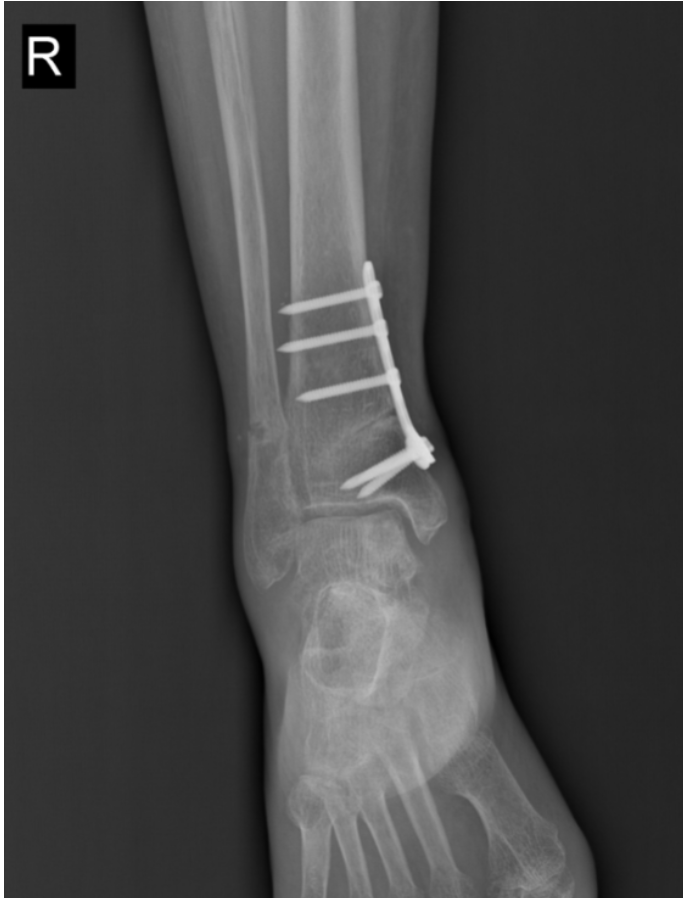

踝上截骨治疗踝关节关节病及距骨骨软骨损伤的手术治疗,对医生手术技术要求高,需要对踝足部的力线及平衡调整有丰富临床经验,术中要有很强应变能力。在李恒和足踝外科小组配合下顺利完成!

术后复查X线,非常完美。李恒提醒,踝关节是人体中负重最大的关节,出现问题会给生活带来极大的痛苦和不便,崴脚并非小事,若早期处理不当,错过最佳治疗时机,轻则遗留慢性疼痛,重则导致创伤性关节炎、慢性踝关节不稳等后遗症,所以“走路看路”+“积极的运动锻炼”,预防踝关节损伤非常重要!